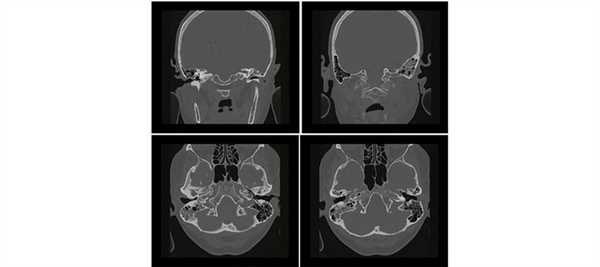

Всем пациентам проводили КТ и МРТ височных костей. КТ височных костей была выполнена полипозиционно в коронарной и аксиальной проекциях с шагом 0,5 мм и МРТ — в стандартных отведениях в SEFSE FLAIR Т1 и Т2 взвешенном изображении в аксиальной, коронарной и сагиттальной проекциях с акцентом на внутреннее ухо.

У 5 пациентов 1-й группы отмечалисьпосттравматические изменения височных костей (у 4 процесс носил односторонний характер, у 1 — двусторонний): у пациента с двусторонним поражением височных костей имели место разрыв и дислокация цепи слуховых косточек, изменений в структурах внутреннего уха выявлено не было. У остальных 4 был диагностирован поперечный перелом пирамиды височной кости: линия перелома проходила через область лабиринта и хорошо определялась на томограммах, при этом у одного из этих пациентов была обнаружена полная облитерация улитки, у другого был найден участок костной плотности в преддверии (давность травмы составила 25 и 8 лет соответственно).